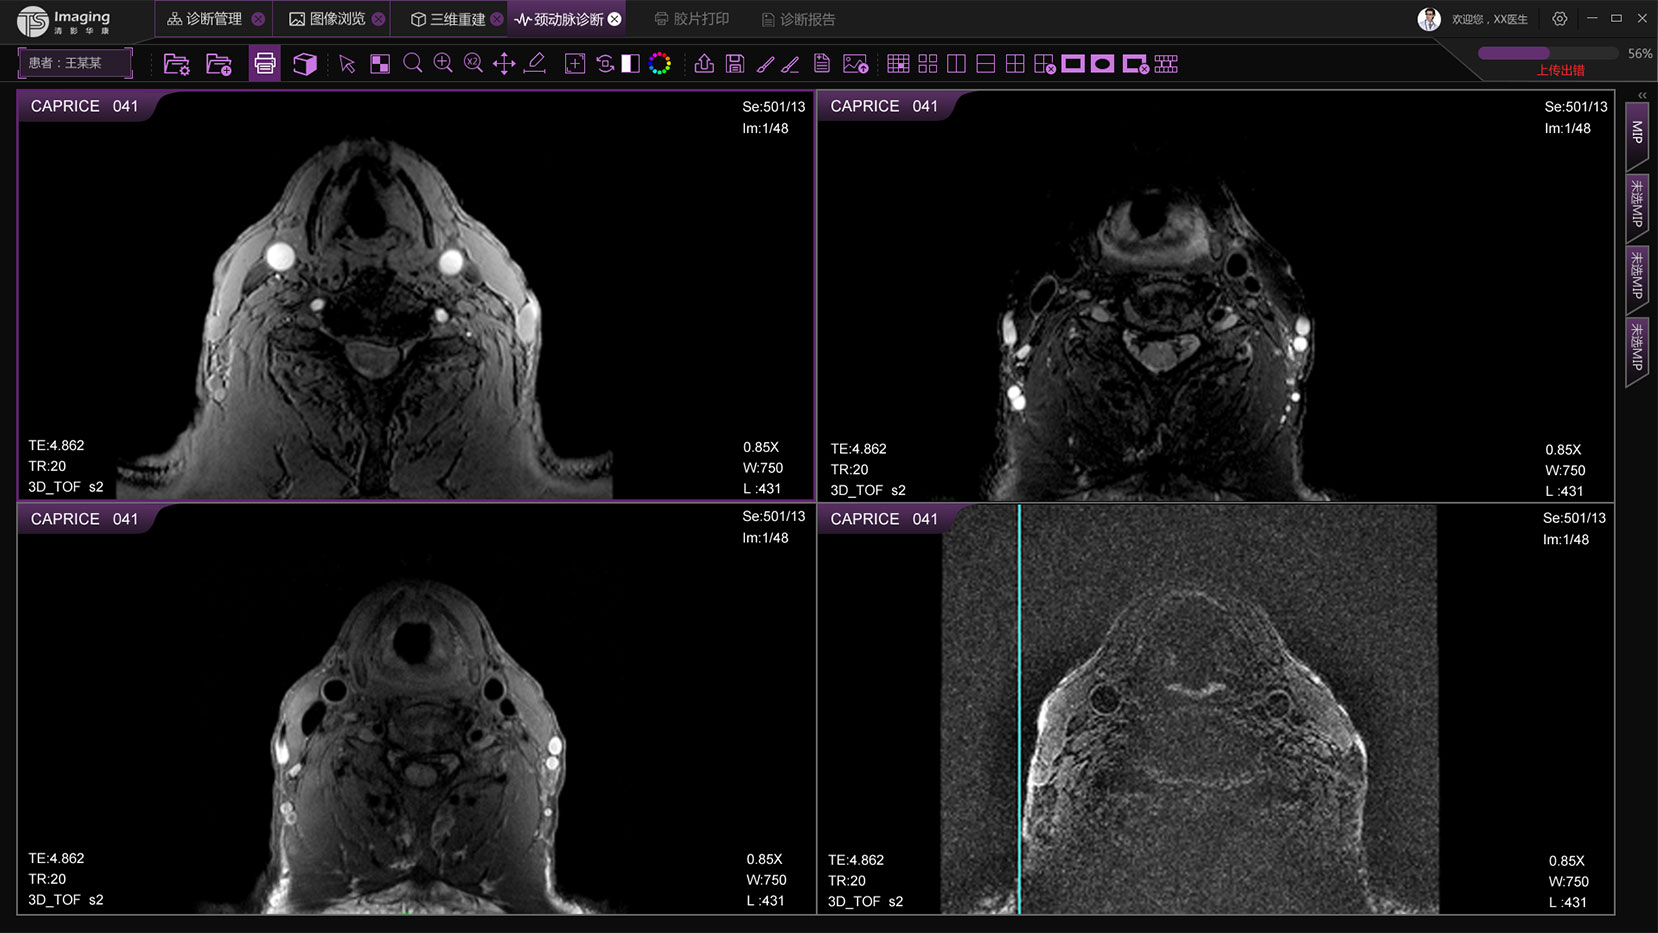

頸動脈診斷頁面

頸動脈診斷頁面整體布局和三維重建比較相似,最大的區(qū)別是右側(cè)的操作區(qū)域,血管分析都為按鍵操作,通過間隔的大小分成三部分。單層切片除了按鍵還有下拉菜單的操作。